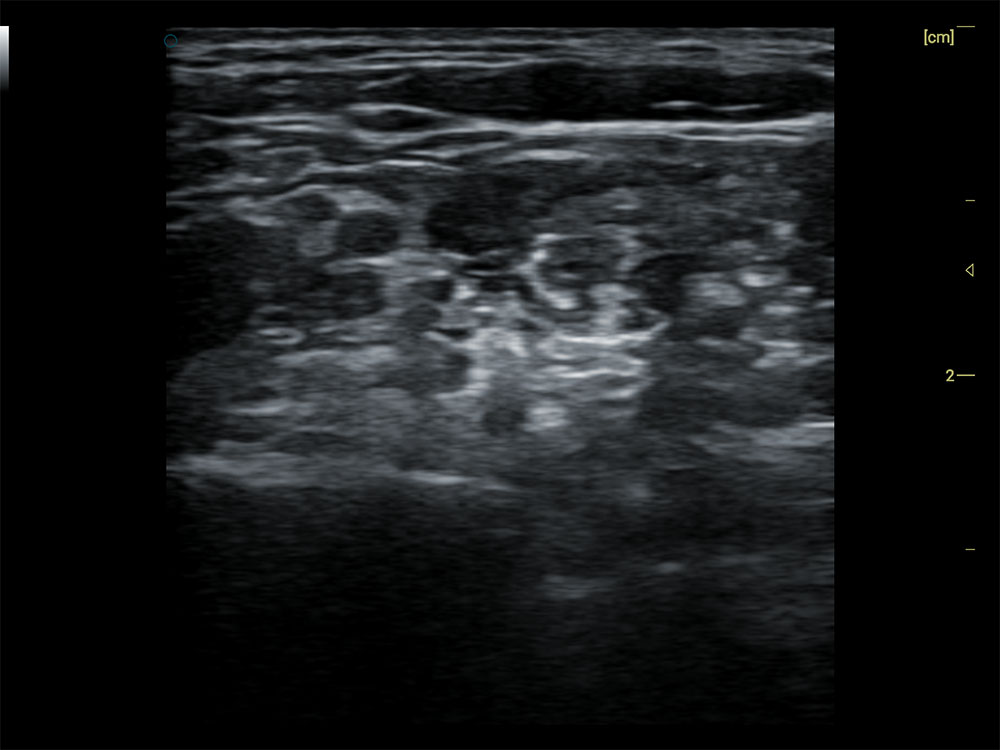

• 探头高灵敏、高信噪比

• 同频探测深度更优